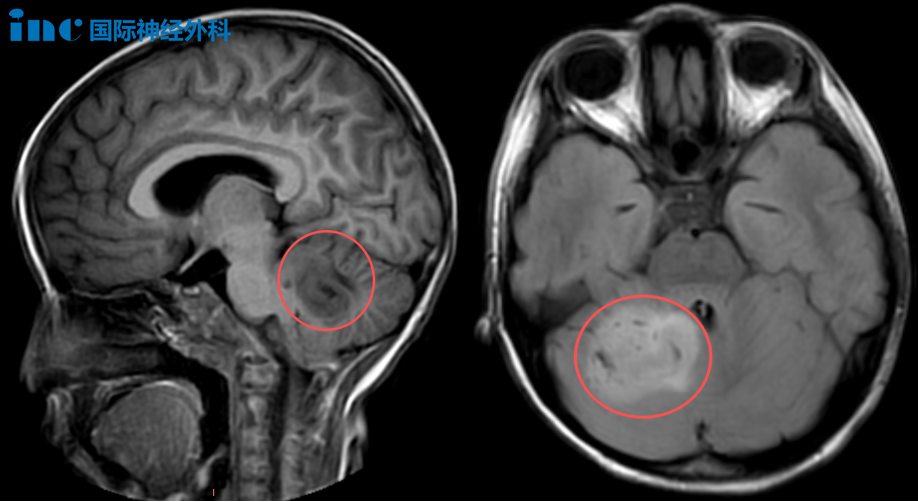

7岁患儿乐乐自出生以来长期存在睡眠障碍。夜间频繁惊醒、双下肢不自主运动,时而突发坐起后倾倒。今年9月,患儿向家长主诉日间头晕及乏力症状。次日因反复呕吐急诊就医,影像学检查发现小脑区巨大占位病变。

后续检查再次证实右侧小脑异常信号,初步诊断为低级别胶质瘤。同期血液检查提示胃肠型感冒,予对症药物治疗后头晕症状缓解。

此前会诊医生提示肿瘤与脑干可能存在粘连,手术难度较大。为争取更好预后,家长咨询巴教授意见并获得不同评估结果:"鉴于病灶体积,手术干预确有必要。即使是低级别肿瘤也存在恶变风险。虽然病变涉及小脑-脑干连接区域,但未侵犯脑干实质。虽然手术具有挑战性,但我能实现肿瘤切除的同时最大程度保留神经功能和生活质量。"

10月20日,由巴教授主刀,苏州大学附属儿童医院神经外科团队配合,应用术中导航及超声技术精确定位肿瘤边界,在神经电生理监测保障下顺利完成肿瘤切除术。术后病理证实为低级别胶质瘤,家属忧虑得以缓解。